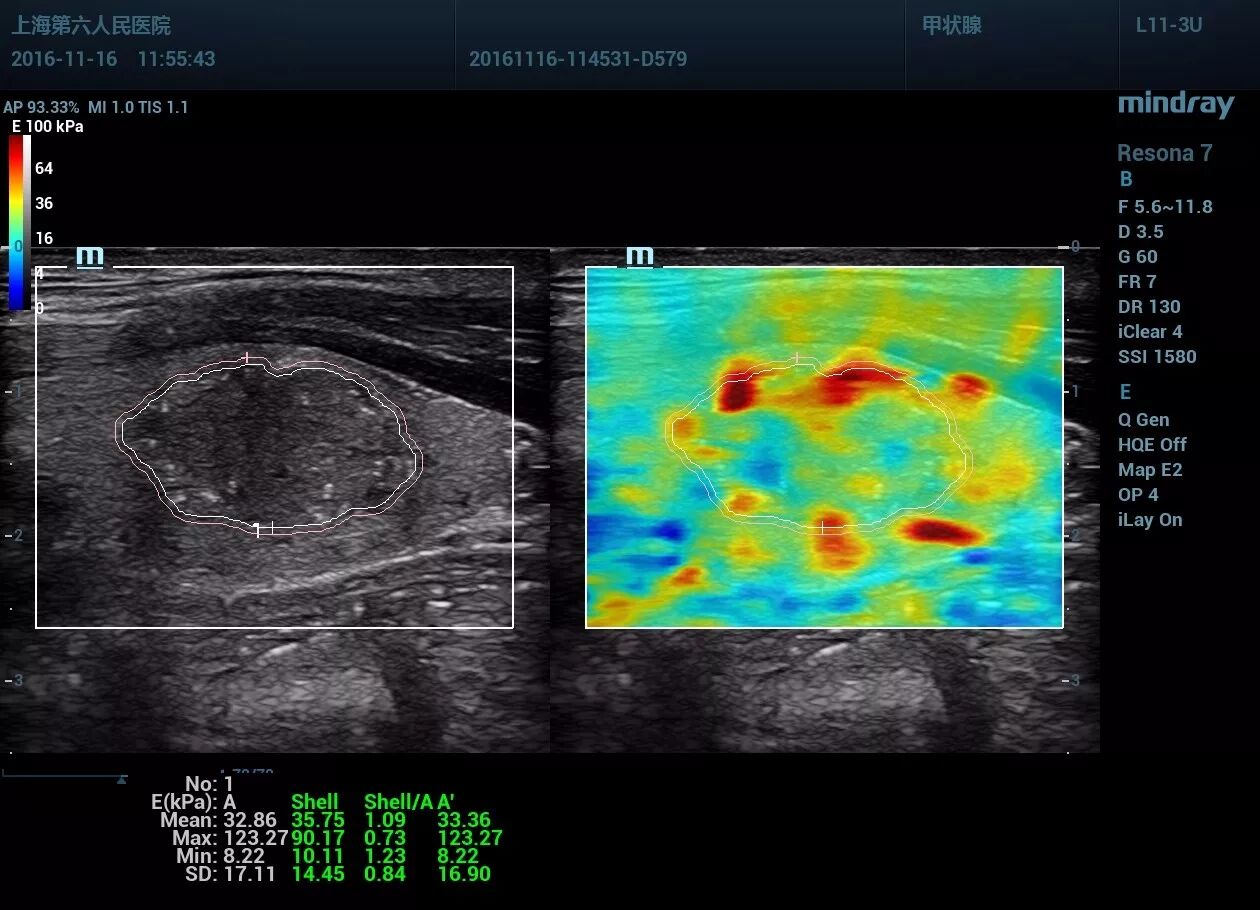

甲状腺左叶见一低回声区,大小约14*13*18mm,形态尚规则,部分边界欠清晰,内见点状强回声。CDFI显示血流信号丰富。左侧颈部VI区一淋巴结见高回声区。

应变式弹性评分:5分。剪切波弹性,横断面Emax94kpa,纵断面Emax123 kpa,远远大于良性病变的杨氏模量范围。纵切面显示肿块周边见深红色的不连续“硬环”。